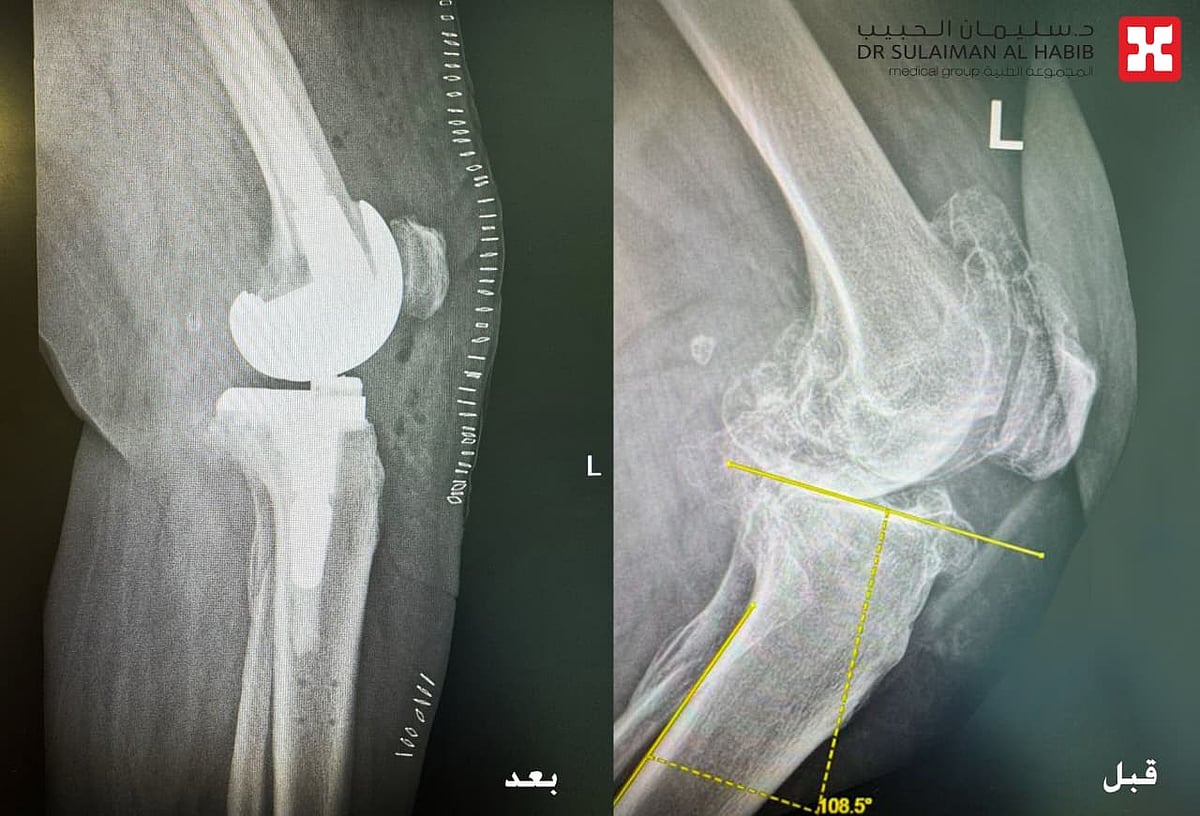

مستشفى الدكتور سليمان الحبيب بالخبر يُجري عملية زراعة مفصل معقدة بتقنية “الروبوت الجراحي” لإعادة قدرة المشي لثمانينية

نجح مستشفى الدكتور سليمان الحبيب بالخبر، وعبر تقنية الروبوت الجراحي “Robotic Surgery”، في إنهاء معاناة مراجعة تبلغ من العمر 84 سنة، كانت تشكو من ألم حاد ومزمن في مفصل الركبة اليسرى، أفقدها القدرة على المشي. ذكر ذلك الدكتور محمد سكيك استشاري طب وجراحة العظام واستبدال المفاصل، رئيس الفريق الطبي المعالج الحاصل على الزمالة البريطانية والكندية.